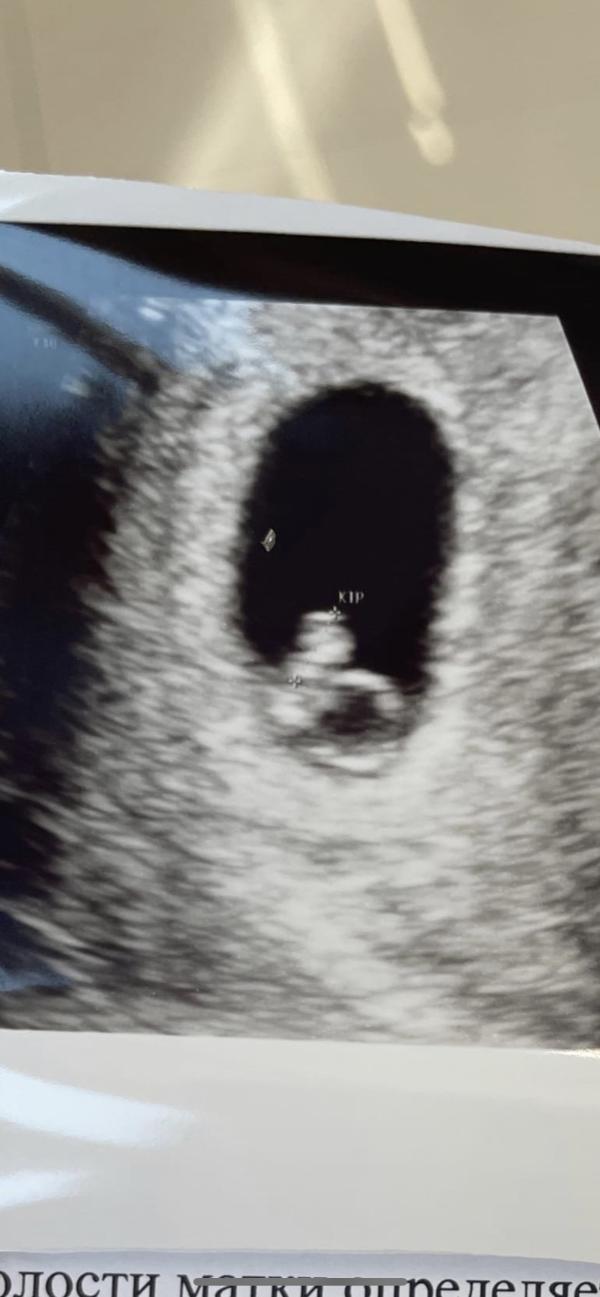

2 ✌скрининг ✅.

По УЗИ всё хорошо, идём по сроку!!!

Сказали кто у нас будет 🤰